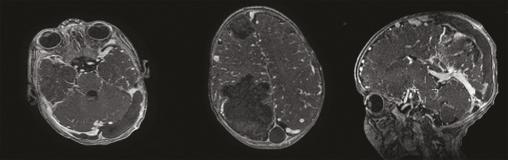

Ce nourrisson de 5 mois était admis aux urgences pour une crise convulsive généralisée. Issu d’un mariage consanguin, il était né par voie basse, sans notion de souffrance néonatale ni antécédents pathologiques notables. L’examen clinique trouvait un syndrome méningé fébrile. Un bilan biologique, une ponction lombaire, une tomodensitométrie et une imagerie par résonance magnétique cérébrales (fig. 1 et 2) étaient réalisés en urgence. Les prélèvements sanguins et du liquide céphalorachidien avaient un aspect lactescent, en faveur d’une méningite bactérienne, et le bilan lipidique était très perturbé : hypercholestérolémie totale à 17 g/L avec un LDL-cholestérol très élevé et un HDL-cholestérol très bas. L’imagerie montrait des plages lésionnelles parenchymateuses cérébrales droites, frontale et pariétale, de signal graisseux et une thrombophlébite cérébrale des sinus longitudinal et latéraux ainsi que quelques veines corticales de signal graisseux. Le diagnostic d’hypercholestérolémie primaire était posé. Le nourrisson était hospitalisé en réanimation et mis sous régime hypolipidémiant.